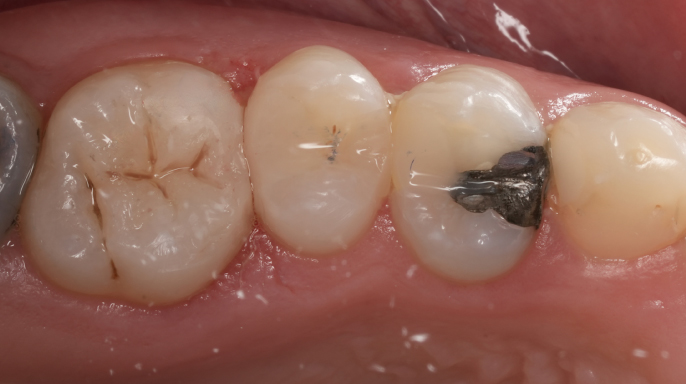

Interview / reportážVyžadují všechny prasklé zuby ošetření kořenových kanálků? Jak brzy po endodontickém ošetření by měl prasklý zub dostat korunkovou rekonstrukci? Jak lze předpovědět prognózu prasklého zubu? To jsou otázky, které často slýchám od přátel i kolegů.

EndodonciePacient se dostavil do ordinace, nespokojený s estetickým výsledkem korunek na zubech 24 a 25. Klinické vyšetření prokázalo nevyhovující marginální uzávěr u obou korunek, a proto bylo indikováno zhotovení nových protetických rekonstrukcí.